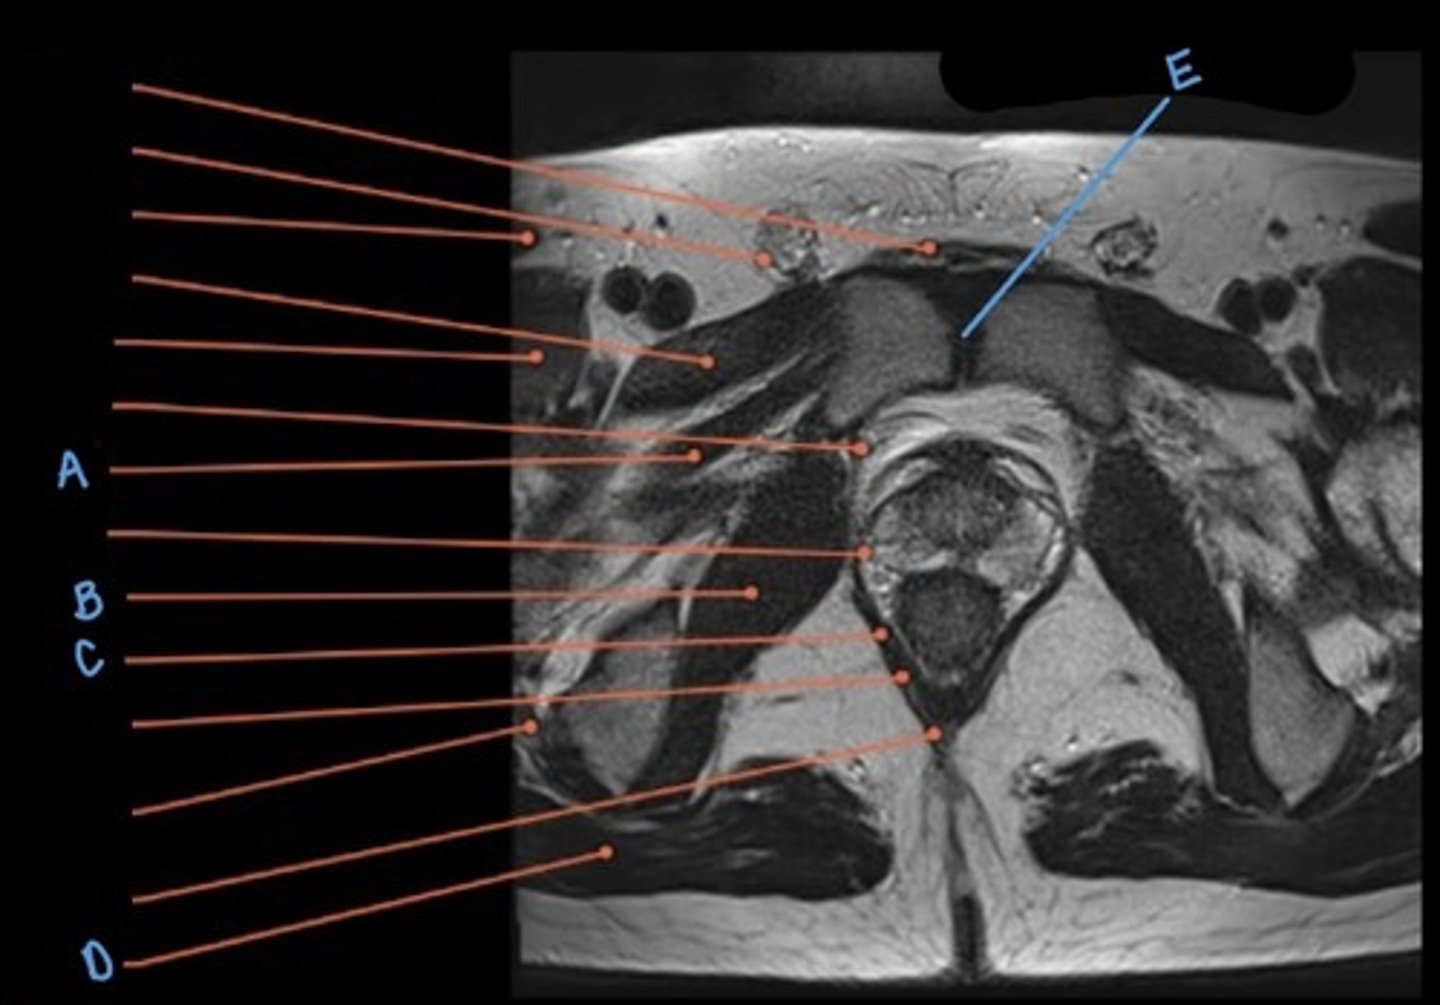

A

obturator internus muscle

B

levator ani muscle (pubic diaphragm)

C

gluteus maximus muscle

D

pubic symphysis

E